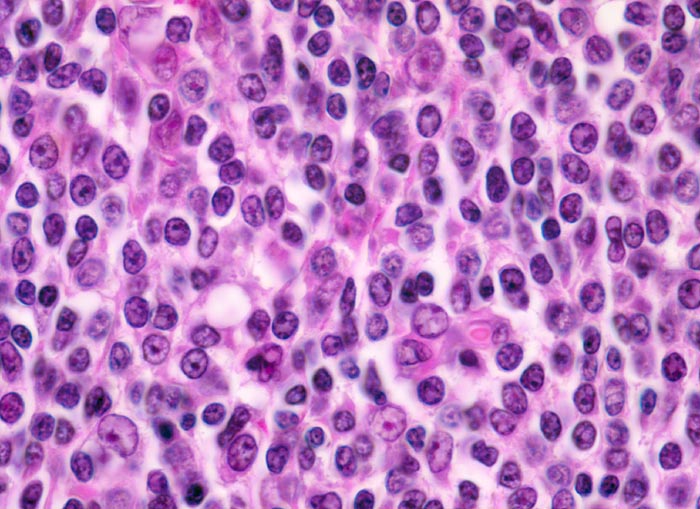

extranodales Marginalzonenlymphom vom MALT-Typ

maligner Tumor

Magen

Das neoplastische Infiltrat besteht aus kleinen zentrozytoiden Zellen mit leicht entrundeten Kernen und wenig Zytoplasma. Eingestreut einzelne immunoblastäre Zellen.

Histologie

400